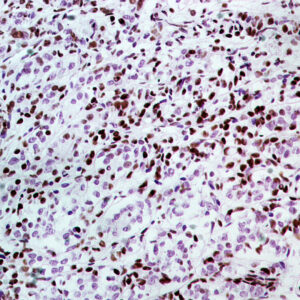

BioGenex has pioneered the development of miRNA research and diagnostics tools with leading-edge products. Currently, we offer over 240 ready-to-use (RTU) Super Sensitive™ Nucleic Acid (SSNA) miRNA ISH probes for accurate and early tumor diagnosis. These probes are sensitive enough to detect low-abundant miRNA(s) that are often required to identify biomarkers. They have a high melting temperature enabling stringent washes to remove non-specific binding. BioGenex miRNA probes are dual-end labeled with an anti-fluorophore to amplify the signal and yield clean and intense staining.